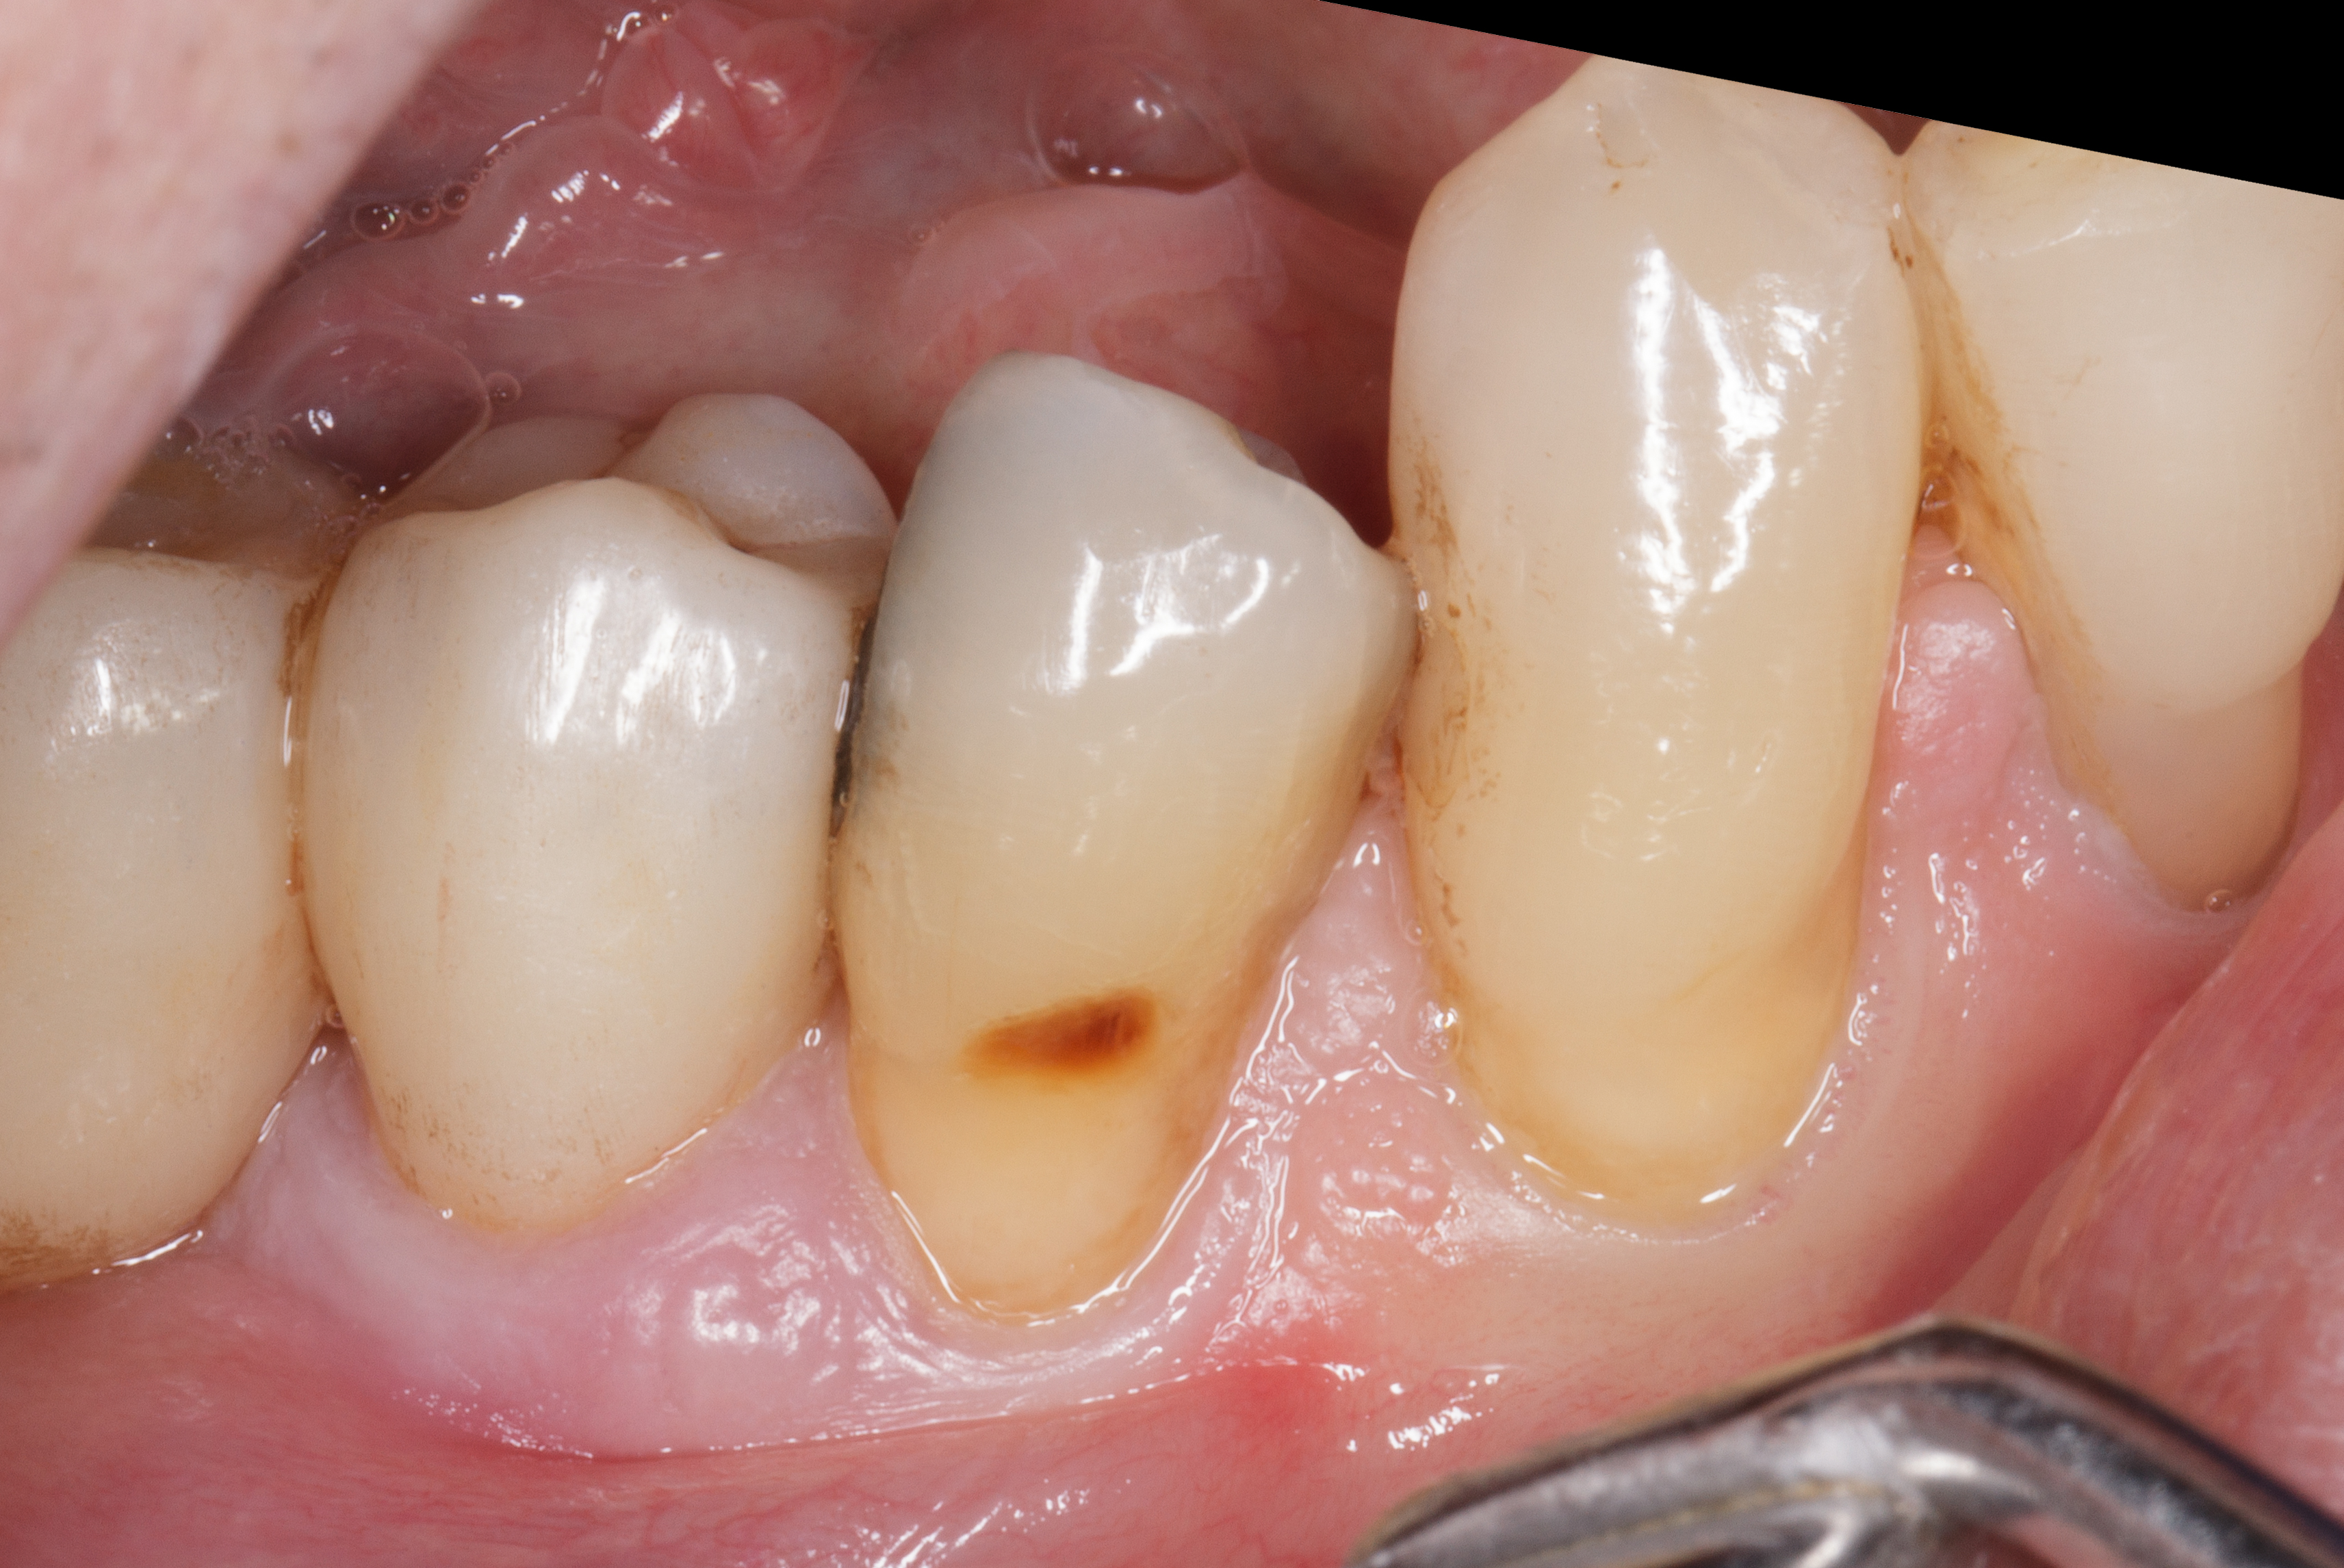

Il paziente si presenta alla nostra osservazione con l’elemento dentale 4.5 fratturato in senso verticale.

La situazione clinica appare essere la seguente: 4.5 elemento di ponte protesico con 4.6 in estensione, presenza di fistola vestibolare, sondaggio di 7 mm mesiale a radice di 4.5 fratturata con fuoriuscita ematica e purulenta (Figure 3-4).

Dopo terapia causale del quadrante inferiore destro e miglioramento della situazione parodontale, si procede alla rimozione delle corone protesiche 4.5 e 4.6.

Si evidenzia chiaramente la frattura radicolare corono-apicale dell'elemento 4.5 (Figure 5-6).